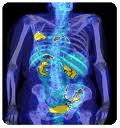

При исследовании органов пищеварения и печени применение контраста помогает обнаружить распространившийся злокачественный процесс и выявить его источник. Важность этого исследования невозможно переоценить. В случае, когда, например, рак желудка дает метастазы в поджелудочную железу или печень, новые очаги должны лечиться, как рак желудка. Это связано с тем, что новые раковые клетки имеют то же строение и свойства, что и первичная опухоль.

Очевидным преимуществом применения контраста в ПЭТ/КТ исследованиях является обнаружение метастазов. В некоторых случаях врач онколог предполагает их наличие, но не может определить точное месторасположение. Йодсодержащие препараты окрашивают злокачественные новообразования и делают отчетливо видимыми.